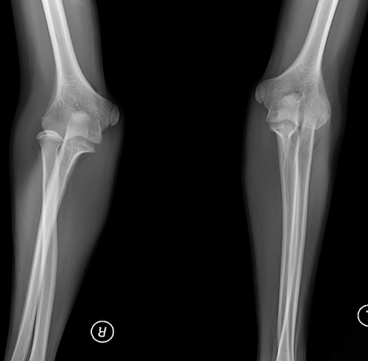

РОЗПІЗНАЙТЕ КІСТКУ. ПЕРЕЛОМ ЯКОЇ ЇЇ ЧАСТИНИ ВИ БАЧИТЕ НА РЕНТГЕНОГРАМІ?

варіанти відповідей

ULNA

RADIUS

FEMUR, ШИЙКА

ПРОКСИМАЛЬНОГО ЕПІФІЗА

ДИСТАЛЬНОГО ЕПІФІЗА

ДІАФІЗА

ЛІКТЬОВОГО ВІДРОСТКА

ПРОМЕНЕВОГО ВІДРОСТКА